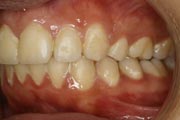

Crowding

Before